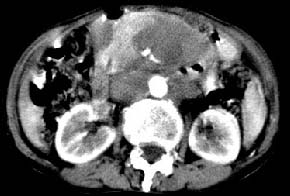

腹膜后淋巴瘤融合成团并包绕周围血管

从发病部位(腹主动脉周围)及增强方式(均匀轻度强化、少量坏死)和病变形态(较大、多结节形)符合腹膜后淋巴瘤,建议颈部病变活检。

我的第1诊断还是考虑是淋巴类病变1}。从病灶形态上看不是很规则,但其更向是多个结节的融和,其内有少许坏死,整个病灶的强化不是很明显,临近左恻肠间隔有增厚,2}我认为更重要的一点的是肠系膜有明显增厚呈片状。3}患者的脾脏不大其未见异常病灶。结合以上几点我首先考虑是转移性{但对此诊断我觉得不足之处;转移性的淋巴结肿大融合为什么没有坏死?}。{另外患者无大便习惯改变及血便,其发现右颈包块在今年过年无意发现}。以上是我的浅分析望各位战友继续讨论!谢谢!!

腹膜后淋巴瘤血管包埋

考虑腹膜后淋巴瘤融合致血管包埋。